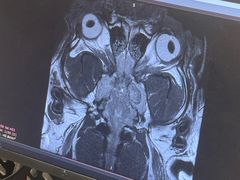

• 北京派仕佳德动物医院·超导核磁·CT·神经科·骨科·内外科·急重症管理中心

• -北京派仕佳德动物医院·超导核磁·CT·神经科·骨科·内外科·急重症管理中心